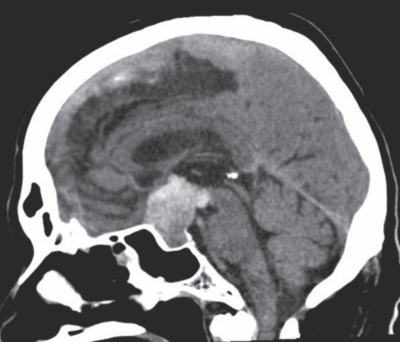

72歳の男性。突然の激しい頭痛と急激な両側の視力低下を主訴に来院した。意識は清明。身長169cm、体重69kg。体温36.8℃。脈拍80/分、整。血圧154/92mmHg。四肢麻痺はない。頭部単純CTの冠状断像と矢状断像を示す。

適切な治療はどれか。

a. 血管内治療

b. 減圧開頭術

c. 経蝶形骨洞手術

d. 開頭クリッピング術

e. 腰椎(髄液持続)ドレナージ